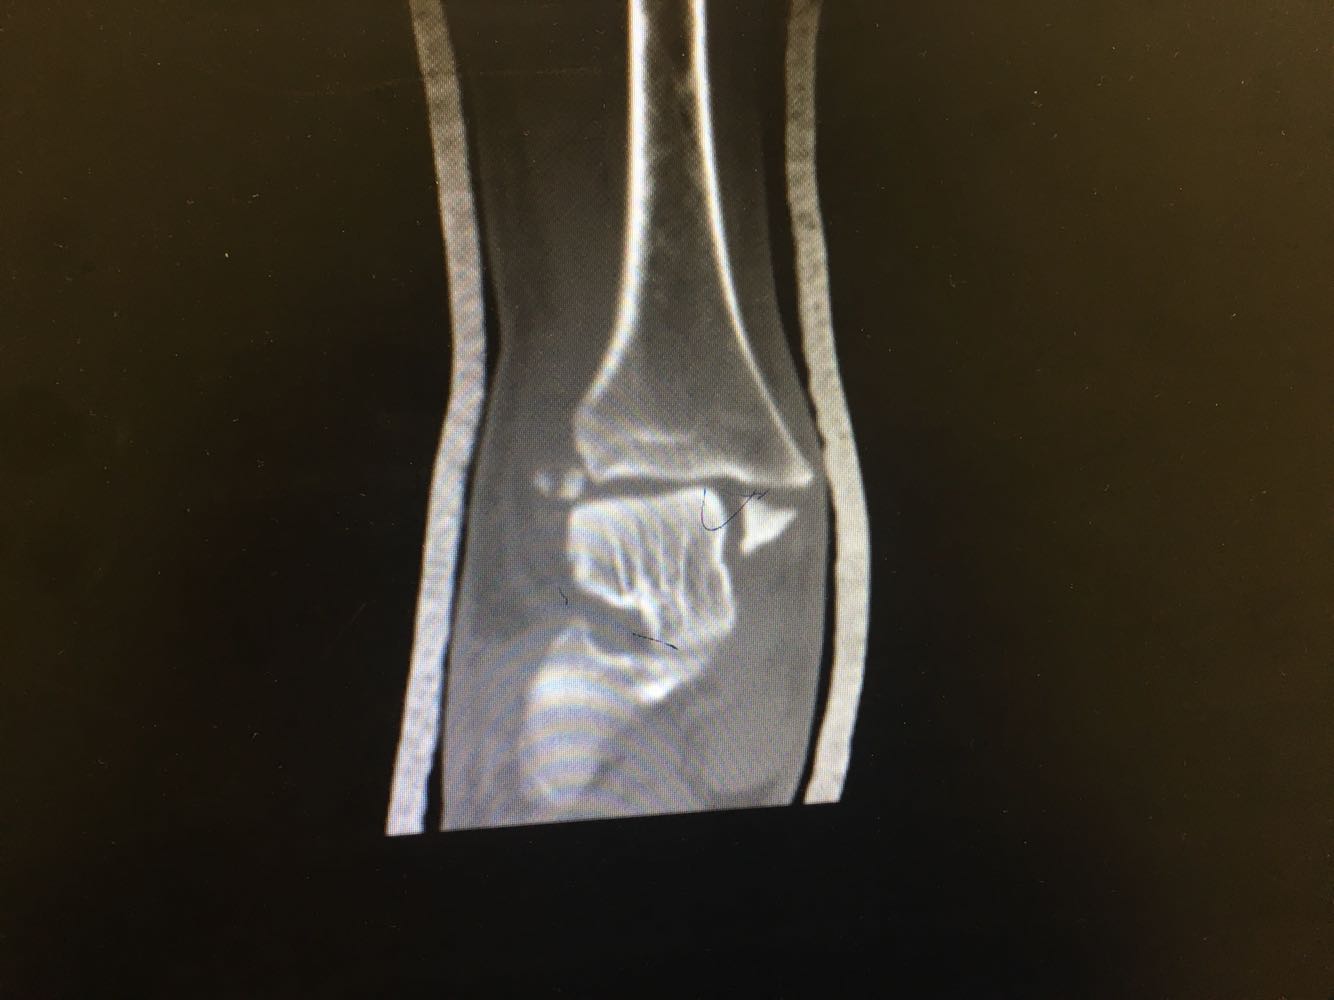

患者,男,54岁。 主诉:外伤致右踝疼痛伴活动受限2天 现病史:患者于2天前不慎扭伤致右踝疼痛,伴活动受限,否认头晕头痛、恶心呕吐等不适,就近医院就诊,查X片示:右踝骨折,予石膏外固定,现为进一步诊治收治入院,发病以来,神清,精神可,胃纳夜眠可,二便无殊,体重无明显变化。

查体:右踝压痛,活动受限,无淤斑淤点,未见皮肤破损,足趾感觉及运动良好。 辅检:右踝部CT

诊断:右侧踝部闭合性骨折 治疗:完善术前检查后行手术内固定